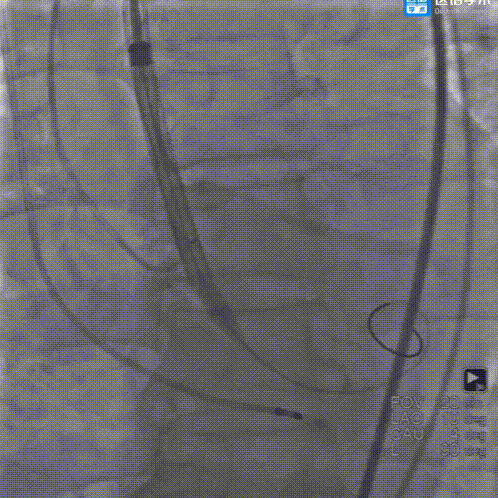

输送器顺利过弓

瓣环零位定位瓣膜

瓣膜释放到工作位

工作位造影评估